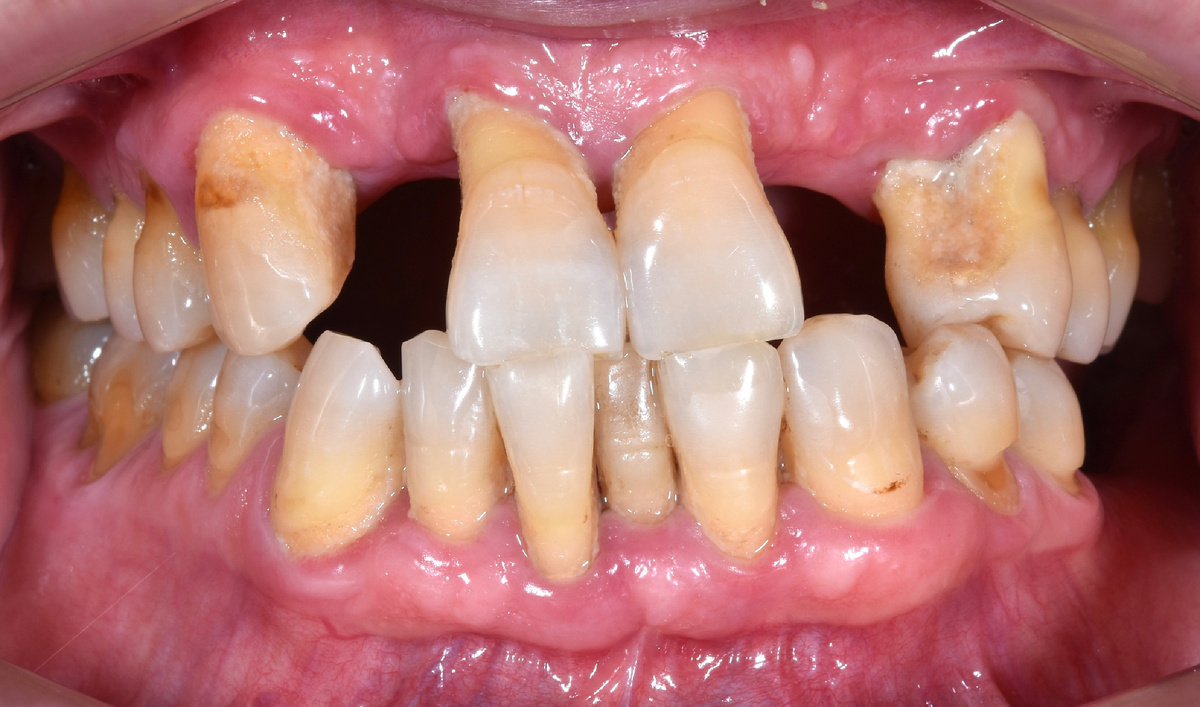

Но тут проблема имеется достаточно серьёзная (и даже не одна). Прикус.

Видете фотографию выше? Видите, что нижняя челюсть впереди челюсти верхней? Зубы же скомпенсировали ситуацию, верхние резцы тяяяяянутся к нижним. Носочками, буквально, цепляются.

Верхняя челюсть "короче" нижней

Зубы в прямом контакте - верх упирается в низ. А челюсти разные по длине. Что делать?

Пациент попросил оставить всё как есть.

Не менять прикус. Врач покумекал, подумал хорошенько. Долго думал, но в случае данного человека оставить как есть посчитал возможным.

Что плохого в "оставить так, как есть" - протез будет с балконом, зубы на верхней челюсти будут так же патологически упираться в зубы на нижней челюсти.